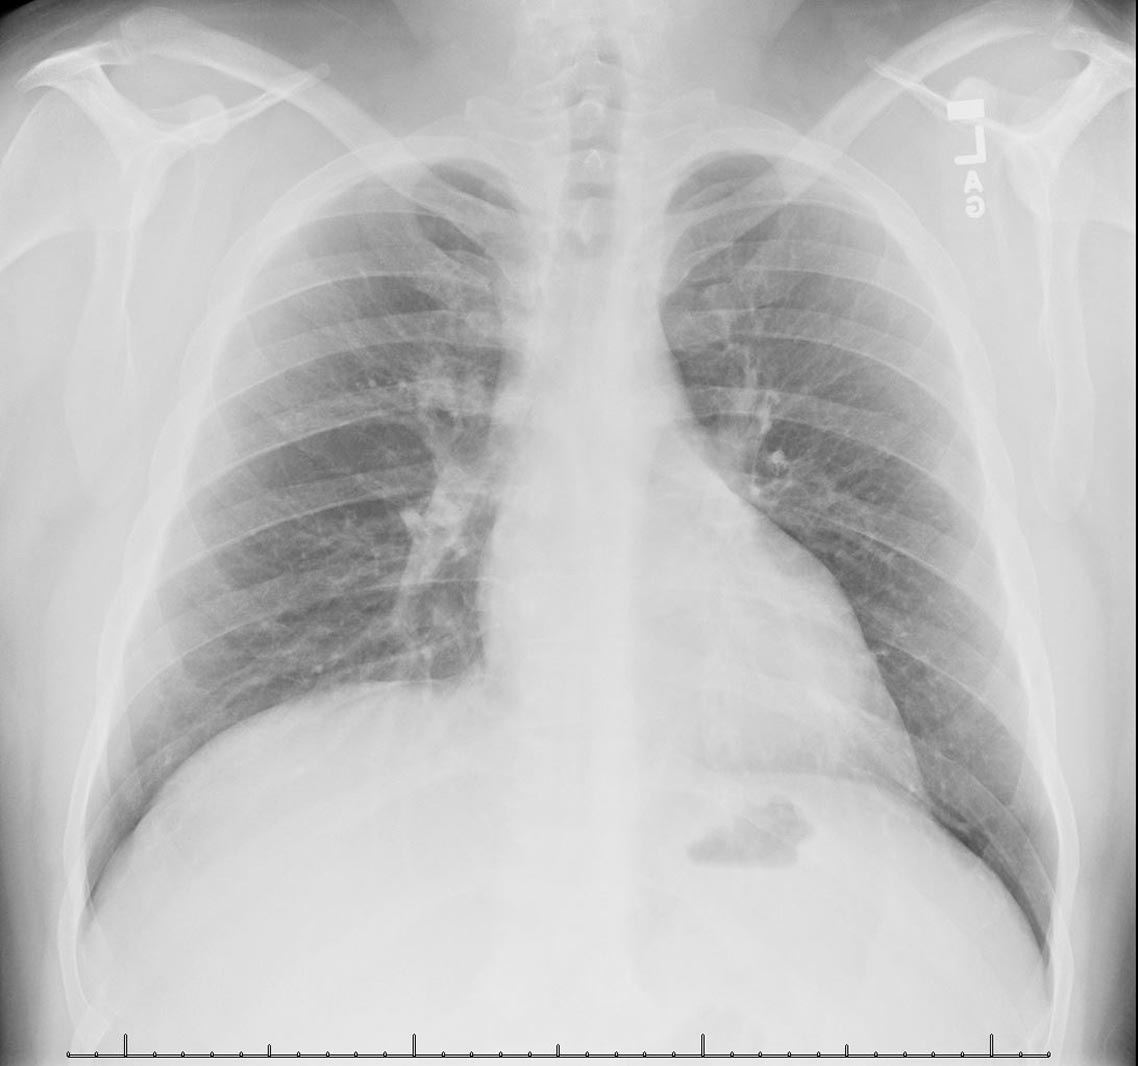

40 y/o female with history of hyperlipidemia, obesity, and GERD presenting with upper abdominal pain. The goals of this case are to evaluate initial evaluation of young female with upper abdominal pain and review ultrasound findings of acute.